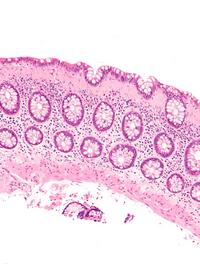

La colite microscopique (CM) regroupe la colite lymphocytaire et collagène avec une incidence croissante en Europe du Nord. Les tableaux [...]